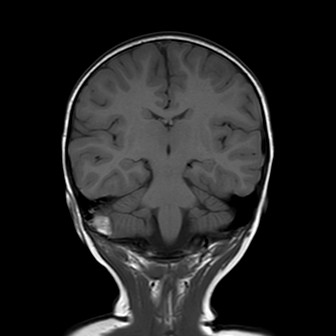

La bambina inizia quindi terapia con enoxaparina alla dose di 1700 UI x 2/die con aggiunta di terapia antibiotica con ampicillina-sulbactam per profilassi. Nei giorni successivi Teresa è stata bene, l’instabilità è andata progressivamente scomparendo senza vomito o cefalea. I successivi controlli all’angio-RM e alla TAC hanno mostrato un rallentamento del flusso in seno sigmoideo destro con tumefazione e netta iperdensità dello stesso, che sono andati progressivamente scomparendo con solo una minima falda ematica residua al giorno della dimissione, dieci giorni dopo il trauma. La terapia è stata dimezzata e poi interrotta dopo tre settimane dall’avvio.

La presenza di atassia alla marcia con vomito è un segno tipico della trombosi del seno sigmoideo che, per quanto rara nel bambino dopo un trauma, va esclusa con una angio-RM, non essendo la TAC in grado di visualizzare chiaramente il flusso nei seni venosi, soprattutto se all’immagine si sovrappone la contestuale presenza di un ematoma. Inoltre la progressione dei sintomi neurologici indicava il trattamento del trombo con eparina, a differenza dei casi asintomatici dove è indicata la semplice reidratazione per evitarne la progressione e lo sviluppo di ipertensione endocranica.